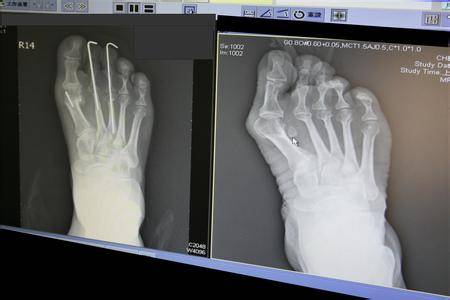

在2011年时,贝嫂就因非常严重的大脚趾外翻,

被专业医生要求放弃高跟鞋,但是她没有听。

大脚趾外翻不仅影响美观,而且会持续疼痛,严重的时候无法走路,如果去做手术矫正,即使手术成功,也留下了难看的疤痕,在那之后只能穿厚底鞋。

女星徐若瑄也曾接受手术治疗大脚趾外翻,她曾透露自己前前后后做了四次手术,还耽误了专辑的发布。